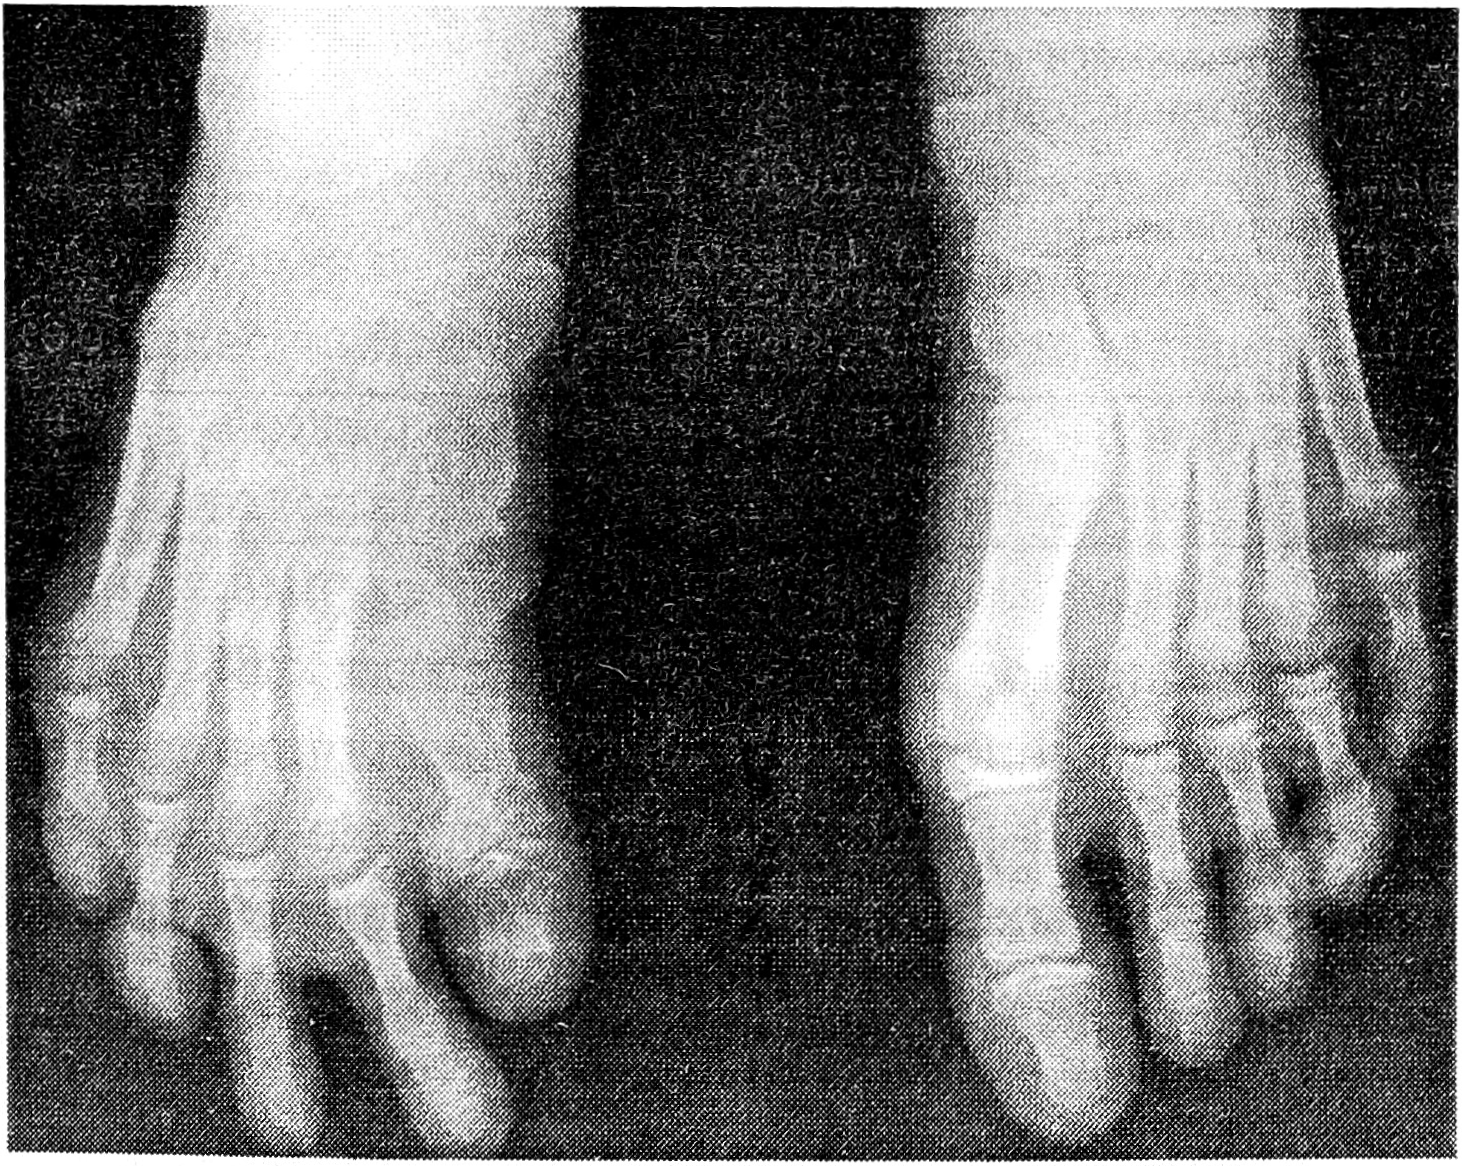

Больная К., 13 лет, поступила в ЦИТО по поводу тотального дефекта I плюсневой кости правой стопы вследствие посттравматического остеомиелита и неоднократных секвестрэктомий, с жалобами на затрудненную ходьбу и нарастающую деформацию I пальца (рис. 1). Первым этапом на I луч стопы был наложен стержневой компрессионно-дистракционный аппарат, с помощью которого создан диастаз на длину пястной кости между клиновидной костью и основной фалангой пальца (рис. 2). После этого 19.09.95 под общим обезболиванием двумя бригадами хирургов произведены замещение дефекта плюсневой кости свободным васкуляризированным малоберцовым трансплантатом, эндопротезирование плюснефалангового сустава силиконовым эндопротезом, пластика дефекта кожи полнослойным кожным трансплантатом (рис. 3). Одна бригада хирургов иссекла рубцы по внутренней поверхности стопы, выделила для наложения микрососудистых анастомозов заднюю большеберцовую артерию и сопровождающие ее вены, подготовила ложе для костного трансплантата. Вторая бригада в это время производила забор малоберцового костного трансплантата длиной 9,5 см с питающей его артерией и венами, мышечной муфтой толщиной 0,8 см. Затем костный трансплантат был адаптирован на стопе и фиксирован к соседним костям спицами Киршнера (рис. 4). Перед выполнением остеосинтеза на дистальный конец трансплантата был «надет» соответствующего размера силиконовый эндопротез, предназначенный для замещения головки плюсневой кости. Наложены микроанастомозы между артерией костного трансплантата и задней большеберцовой артерией и сопровождающими их венами. После снятия сосудистых клипсов отмечено обильное капиллярное кровотечение из мышечной муфты, свидетельствующее о хорошей проходимости сосудистых микроанастомозов и кровообращении в трансплантате. (Последнее было многократно подтверждено в разные сроки послеоперационного периода допплерографически.) На рану наложены послойные швы. Оставшийся кожный дефект размером 1,2 × 4 см закрыт полнослойным кожным аутотрансплантатом. Наложены асептическая повязка и задняя гипсовая лонгета с фиксацией стопы в положении, исключающем малейшее натяжение микрососудистых анастомозов.

Рис. 4. Рентгенограммы стопы через 3 нед после замещения дефекта плюсневой кости васкуляризированным малоберцовым трансплантатом.